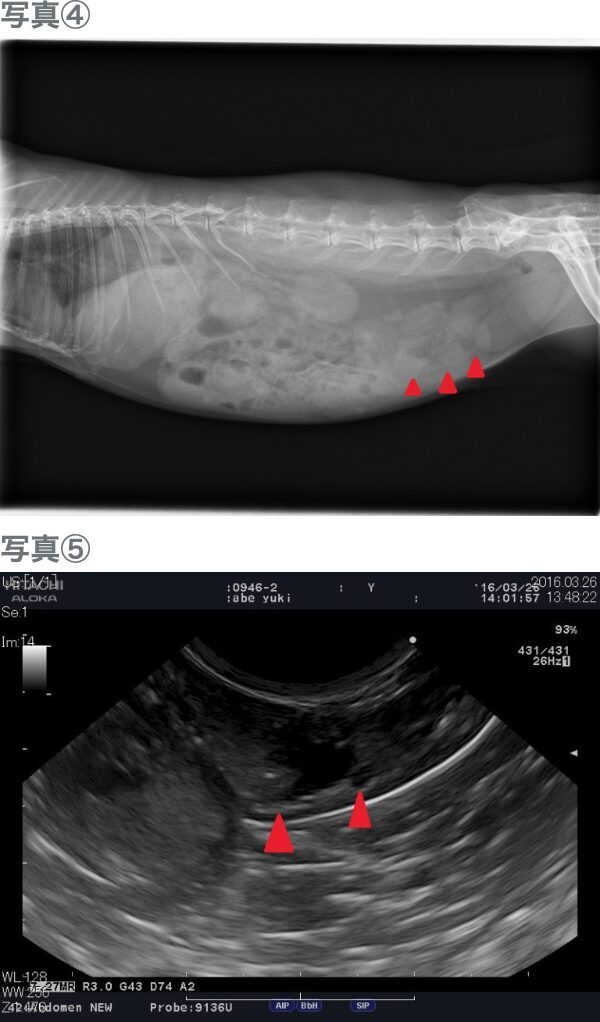

通常レントゲンでは子宮を確認できませんが、腫瘍により腫大してくるとレントゲンで異常な陰影が確認できます(写真④)。また、エコー検査では腫脹した子宮や内部に液体が貯留している様子が確認できます(写真⑤)。